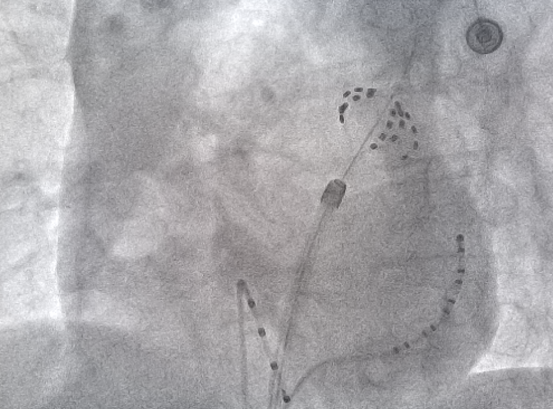

X线下FARAPULSE脉冲消融导管的形态:网篮状